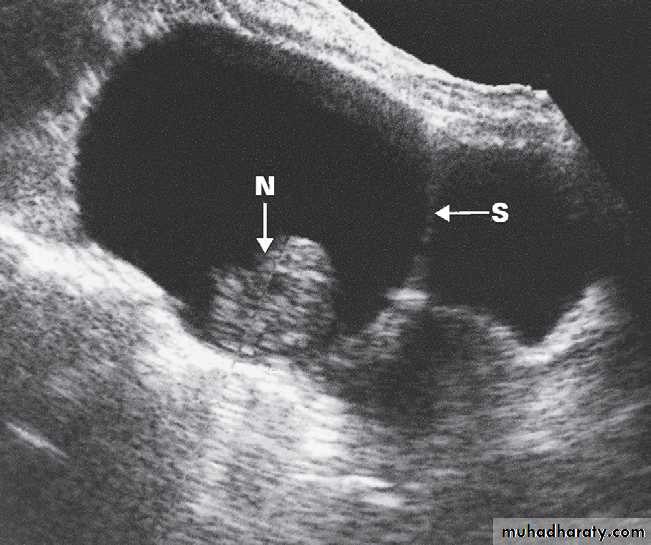

-The typical features of

polycystic ovaries on

ultrasound or MRI include

large volume ovaries

with multiple small

follicles arranged

around the periphery,

forming the appearance

of a ‘string of pearls’ .